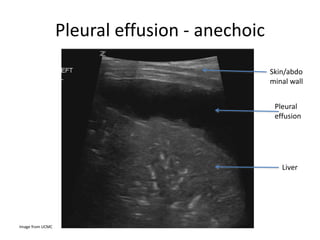

Pleural effusion -anechoic Image from UCMC

Pleural effusion -anechoic Image from UCMC Pleural effusion Liver Skin/abdo minal wall